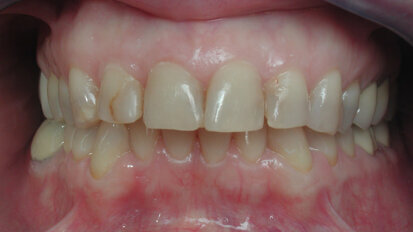

Rehabilitación bucal estética con asistencia de ortodoncia

El Profesor Rony Joubert, experto en odontología estética y reconocido conferenciante internacional, y sus colegas, explican la restauración de un caso ...